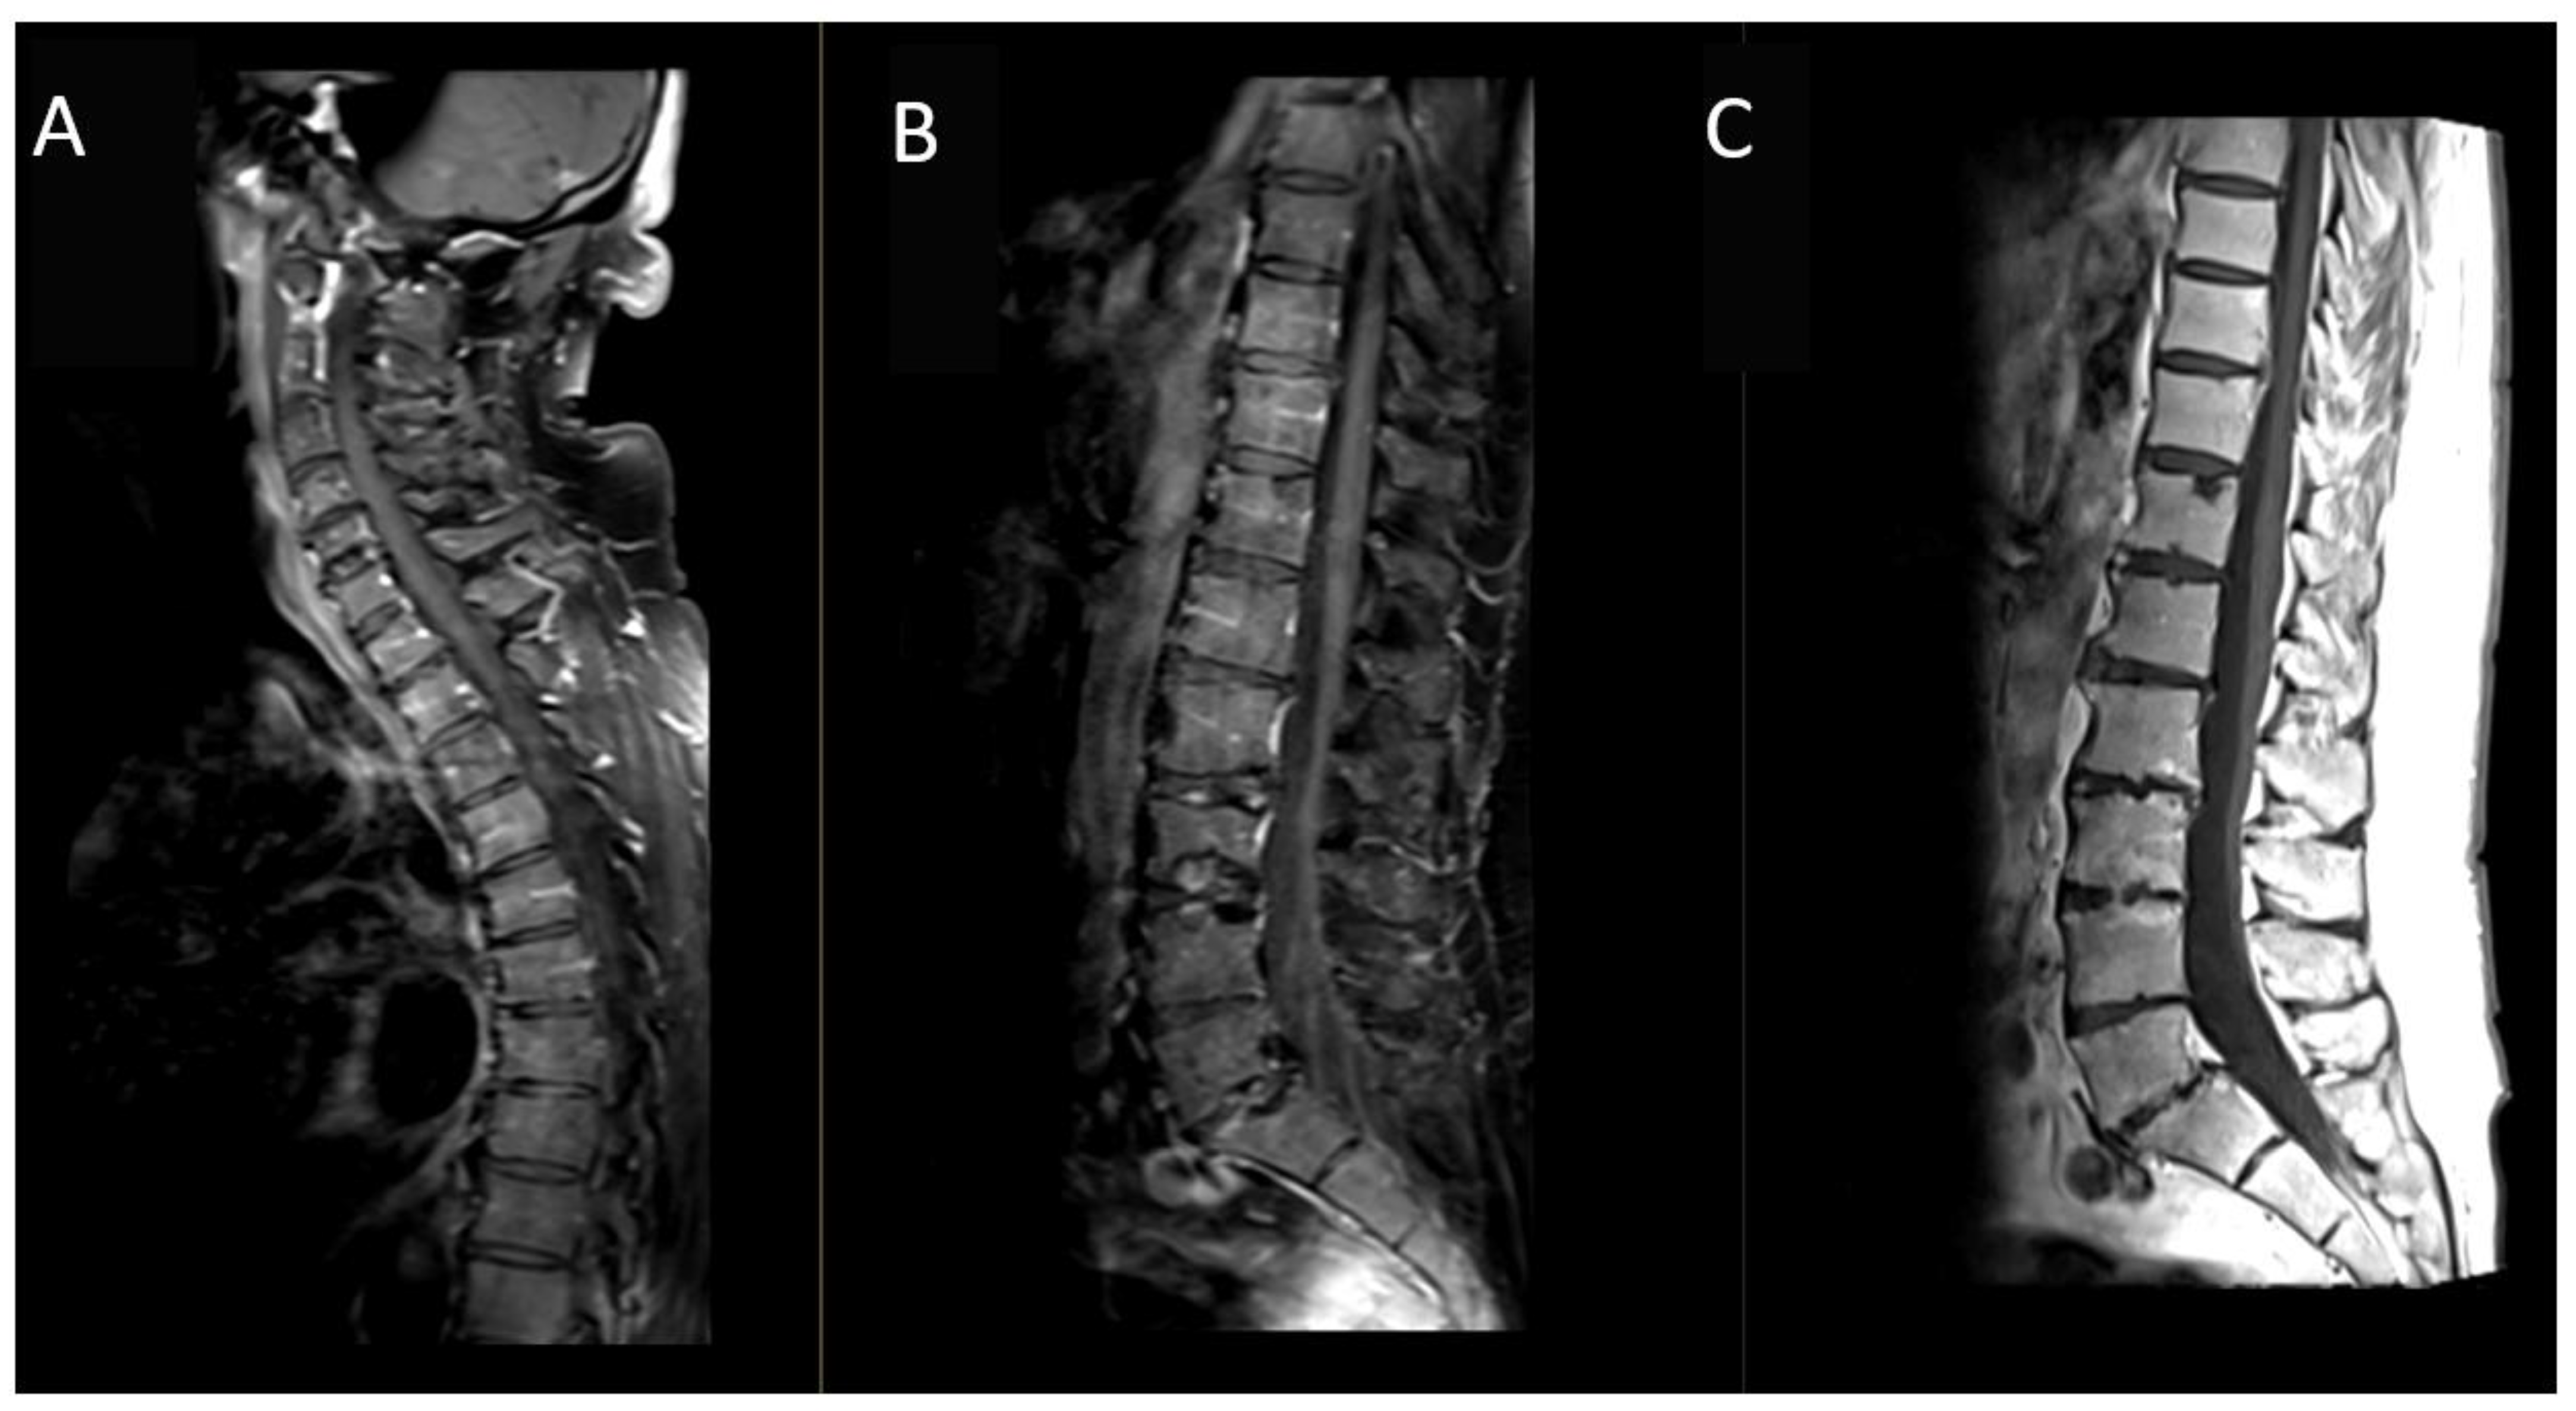

Figure 3.

Post-contrast MRI sagittal T1-weighted images: (A,B) with fat suppression and (C) without fat-suppression. MRI study of the spinal cord and cauda equina did not reveal pathological contrast enhancement attributable to other Bing–Neel syndrome localizations.